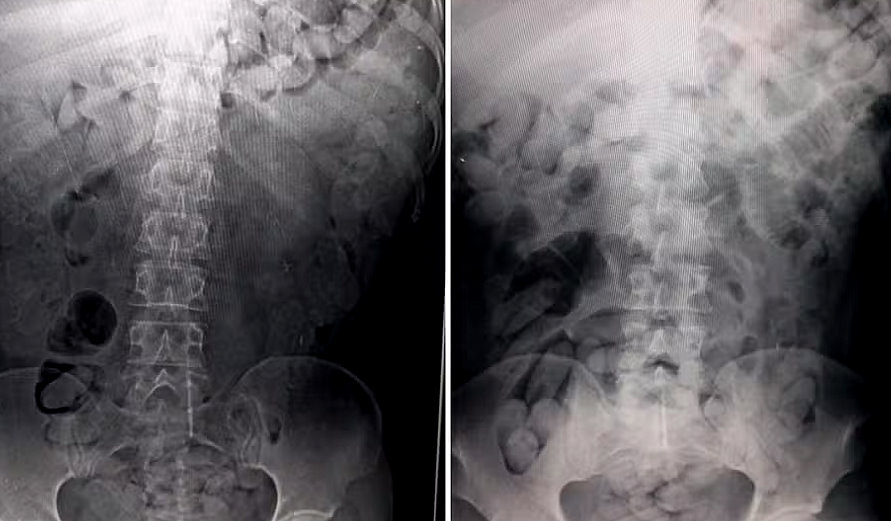

O casal foi encaminhado ao HC, onde radiografias (foto) confirmaram a existência da droga. Para expelir as cápsulas, eles tiveram que passar por lavagem estomacal. A operação durou três dias.